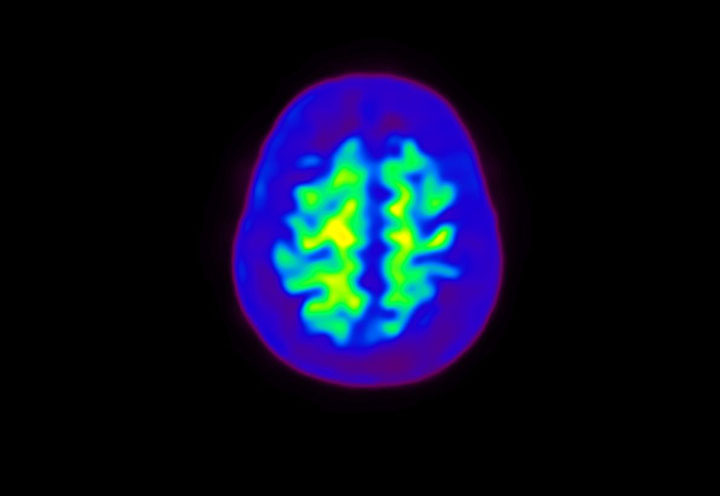

Head / Case4 : Amyloid

Axial

Courtesy : Kindai University Hospital

- Imaging protocol

- Injected dose: 3.21 MBq/kg, 18F-Flutemetamol

- Uptake time: 100 minutes

- Scan time: 20 minutes